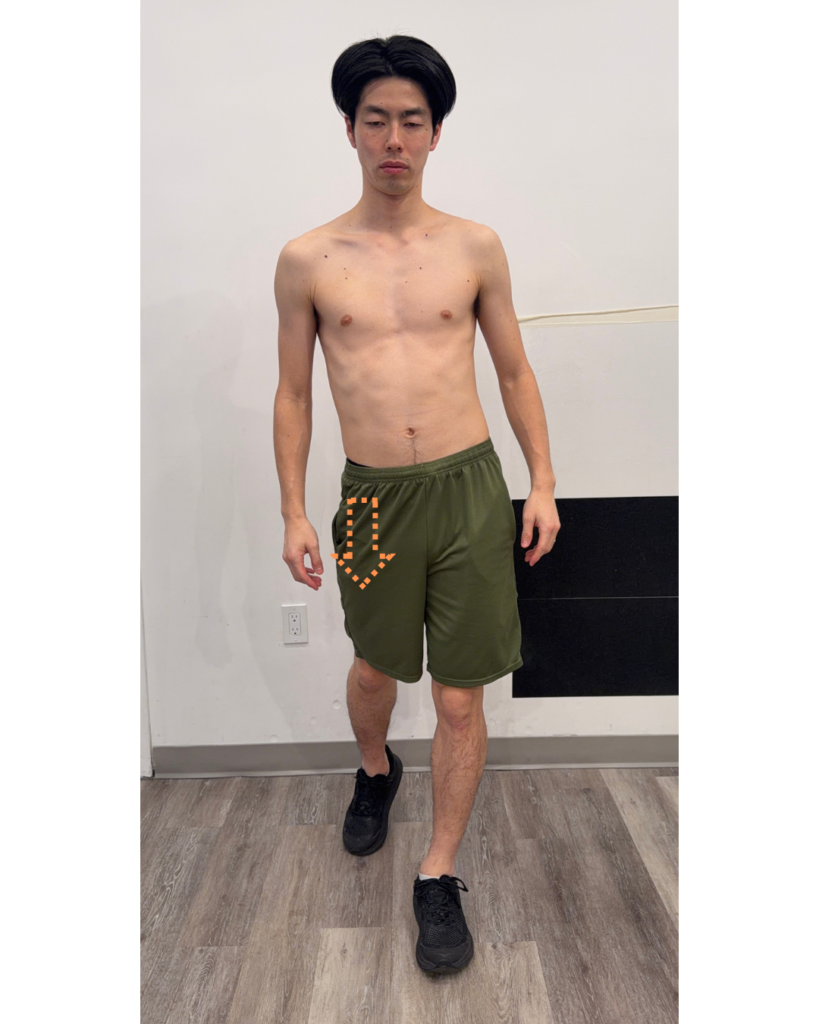

3. Posterior Depression (Midstance to Terminal Stance)

Posterior depression involves the pelvis moving backward and downward on the stance leg.

Role:

- Stabilizes the body over the stance leg

- Enables efficient push-off

- Transfers force for forward propulsion

Muscular connection: glute med, glute max, elongation of the trunk muscles (trunk extension pattern)

Dysfunction:

- A deficit can result in pelvic drop during the opposite swing phase

- Leads to inefficient weight transfer and reduced propulsion

- Commonly associated with overuse of compensatory muscles

Key relationship:

Posterior depression on one side directly supports anterior elevation on the opposite side. Dysfunction here often disrupts the entire gait cycle.

(pelvic hike on the stance leg)